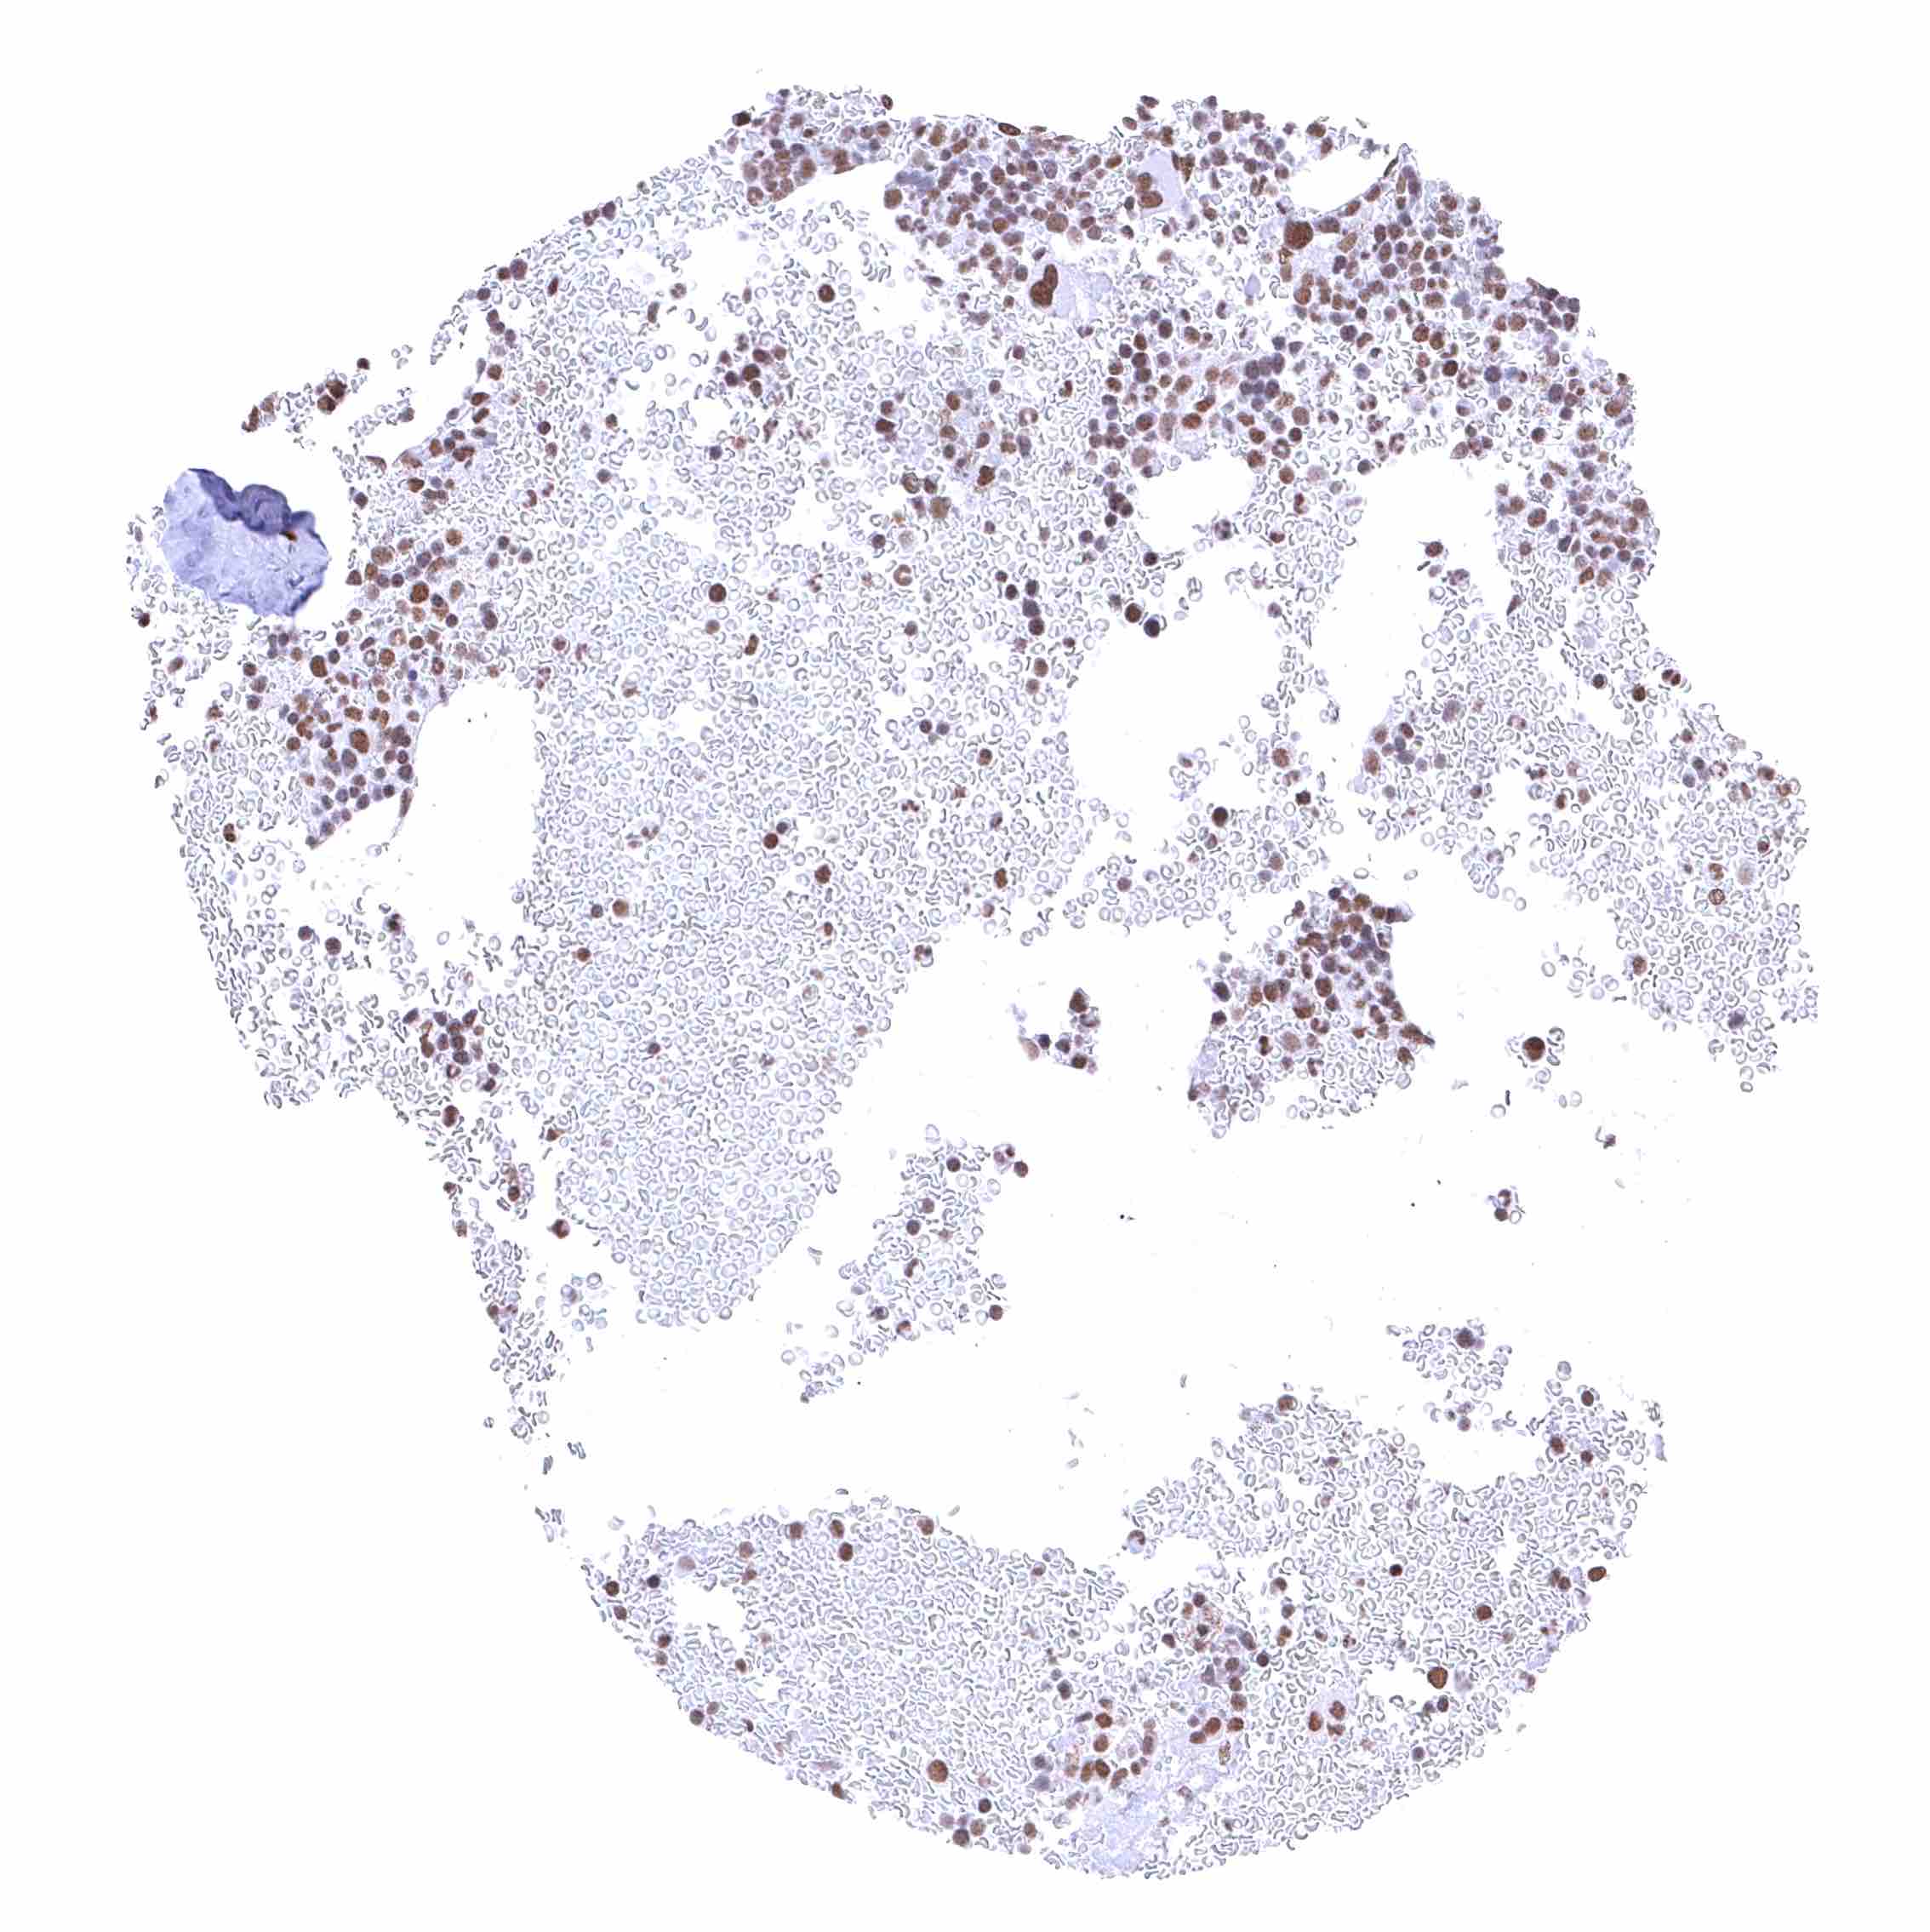

Bone marrow